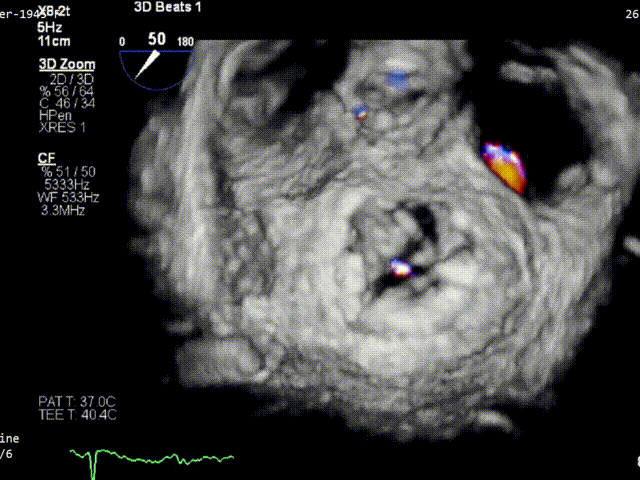

术前3D VIEW

经食道超声提示,患者二尖瓣P1 commissural脱垂、腱索断裂合并重度反流(Carpentier II型/DMR4+)。

二尖瓣后瓣环明显钙化;主动脉瓣轻度钙化;三尖瓣中度功能性反流(FTR2+)。左房明显扩大;左室壁非对称性肥厚,以室间隔基底段肥厚为著(HOCM)。左室整体收缩功能正常。

二尖瓣环AP径33mm,二尖瓣后瓣环明显钙化,房间隔拟穿刺高度40mm;二尖辦脱垂宽度5.7mm,脱垂高度7.7mm,二尖瓣1区前叶长度29mm,后叶长度19mm,二尖瓣2区前叶长度23mm,后叶长度14mm,MVA=4.0cm²。